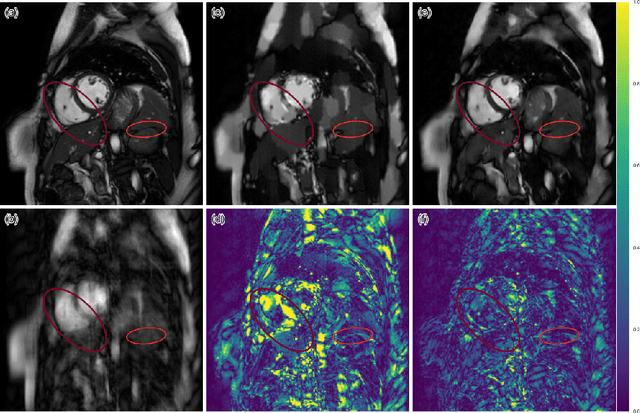

The acquisition of Magnetic Resonance Imaging (MRI) is inherently slow. Inspired by recent advances in deep learning, we propose a framework for reconstructing MR images from undersampled data using a deep cascade of convolutional neural networks to accelerate the data acquisition process. We show that for Cartesian undersampling of 2D cardiac MR images, the proposed method outperforms the state-of-the-art compressed sensing approaches, such as dictionary learning-based MRI (DLMRI) reconstruction, in terms of reconstruction error, perceptual quality and reconstruction speed for both 3-fold and 6-fold undersampling. Compared to DLMRI, the error produced by the method proposed is approximately twice as small, allowing to preserve anatomical structures more faithfully. Using our method, each image can be reconstructed in 23 ms, which is fast enough to enable real-time applications.